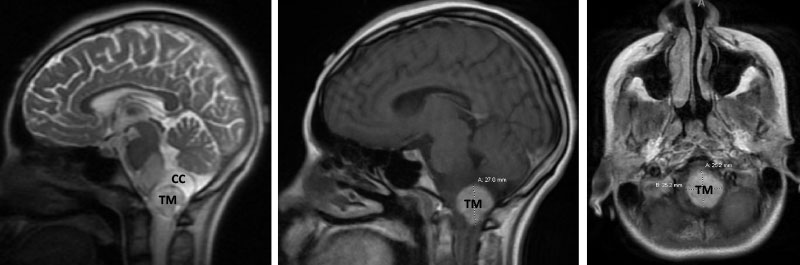

Figure 1. Brain MRI showing tumor mass (TM) with cystic component (CC) and edema (T2-weighted MRI, left) in the lower brainstem and upper cervical cord. Mass with contrast enhancement (post-contrast T1-weighted MRI, middle and right).

A teenage boy presented with 6 months of weight loss and difficulty swallowing. A contrast-enhancing mass in the brainstem and upper cervical cord was found which was suspicious of a symptomatic hemangioblastoma (Figure 1).